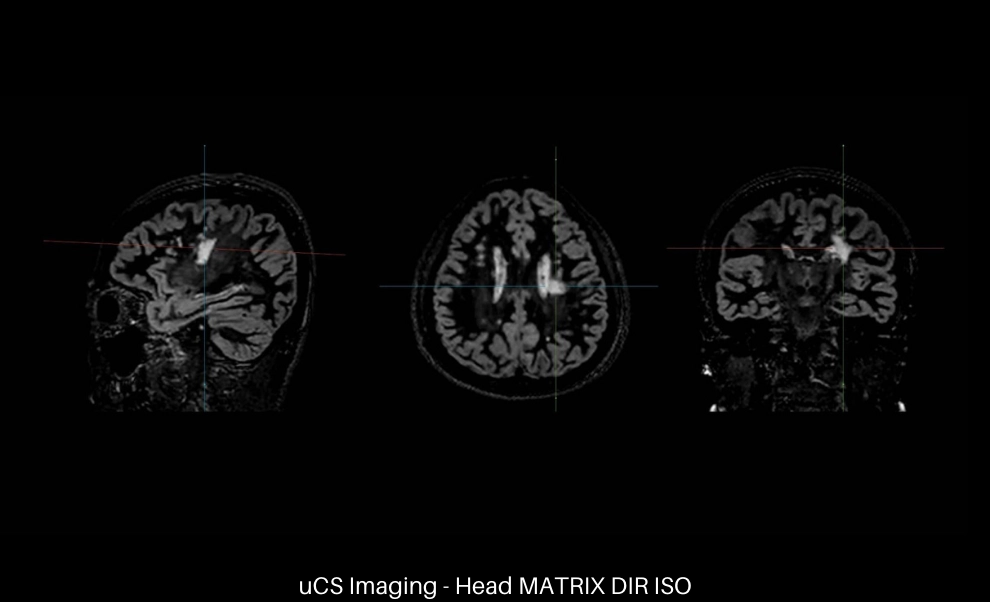

uCS High Spatial Resolution

Static scan with uCS can achieve an acceleration factor of 6 or above in the spatial domain, which allows faster acquisition of high-resolution 3D imaging as well as high detectability for small lesions.